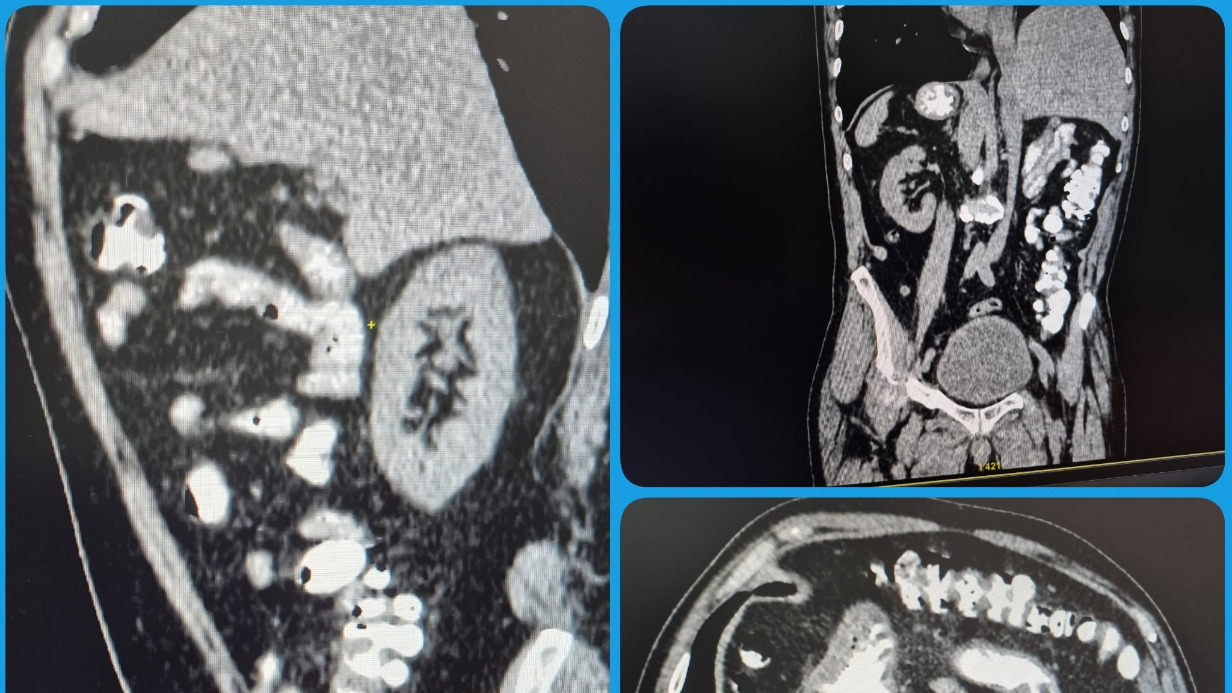

Житель Саратовской области в ходе КТ узнал о необычной анатомической особенности своего тела — все внутренние органы оказались расположены зеркально. Об этом рассказали в пресс-службе Балаковской городской клинической больницы.

По словам представителей медучреждения, такая аномалия встречается довольно редко и является признаком «случайной находки» при обследовании. При этом сам пациент тоже удивился, узнав о своей особенности, так как до этого о ней даже не догадывался.

— Отмечена полная транспозиция органов. На самочувствии пациента это никак не отражается, ни на что не влияет, — передает официальная страница больницы в VK.